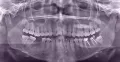

Была на приеме у одного стоматолога, сказал, что нужно удалять нижние восьмерки, одна из них - разрушена. Не больно постучали по нижней левой восьмерке, я выплюнула кусочки зуба. Пошла к другому стоматологу-хирургу, сделала панорамный снимок, сказал, что нужно удалять верхние восьмерки (сказал, что корни целые, но сами зубы - разрушены).

Скажите, пожалуйста, насколько это возможно, какие зубы нужно удалять?